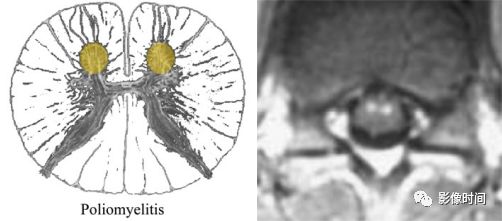

脊髓灰质炎(poliomyelitis):是由脊髓灰质炎病毒引起的脊髓前角运动神经元损害为主,患者多为 1-6 岁儿童。

MRI:

-

双侧灰质前角对称性 T2WI 高信号,类似于脊髓前动脉梗死的「鹰眼征」

急性期明显强化

T2WI双侧灰质前角对称结节状高信号,似「鹰眼」